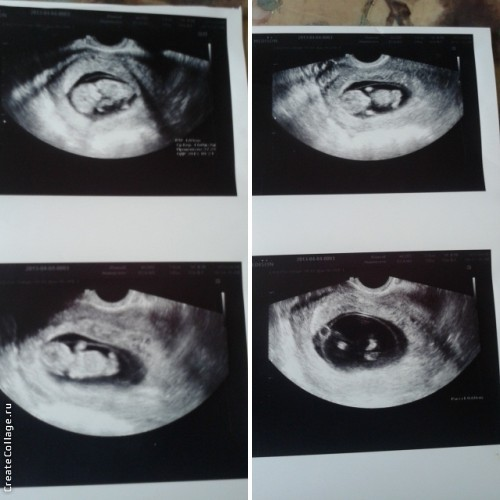

Сходили на первое Узи 2 раза)

Все она посмотрела,проверила,говорит по вашему сроку(тогда она поставила 11 недель)все хорошо)))Сделала нам фоточки)))

И вот сегодня я сходила на Узи в ЖК!!!Начал смотреть и говорил,что то,я ничего не понимаю(Женщина рядом сидит ,записывает все)Смотрел долго так,и больно так было(((Пытался сделать какие то движение этой штукой,чтобы ребенок перевернулся(минут 5)Бестолку(((Отправили меня погулять минут 10(что бы ребенок перевернулся!Пришла,начал смотреть вроде перевернулся и опять говорит,что то ,говорит,мне ничего!Спросила про пол,сказал не видно ничего((Когда уходила,сказал,что в принцепе все хорошо,только просматриволось все плохо!И конечно же на экране мне ничего не показали(как на платном Узи)

Потом сразу пошла сдала кровь ,и на прием с результатами!!!Она мне сказала,то же самое ,что и Узист,но в конце добавила,что нужно здать кровь на свертываемость,что у меня Краевой тип прикрепления пуповины!!!!!!!!!?Она ,что то говорила,я конечно ,же не запомнила и не поняла половину!Поняла,то ,что опасного ничего нет,но могут быть ослажнения,а могут и не бть!Вот такой был ответ!!!Ну и размеры всего прикрепляю,вдруг кому ,то будет интересно)